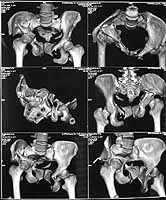

On Jan 26, 2005 the right wing was osteotomized, its segment with the

acetabulum was moved downwards, the ilium was plated, and pelvic external

fixator with femoral extension applied (left image).

After wound healing, anterior reconstruction was performed, iliosacral

screws inserted, the femoral frame removed.

To date wounds healed, the patient walks with crutches, no

weight-bearing at the right side (rest images).

I hope that she'll be better...it's hard to see much on the images with the frame structure on it.